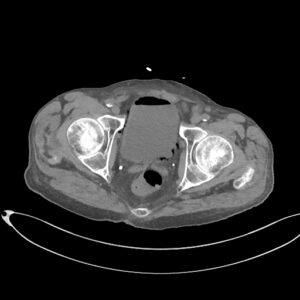

CAZ nr 131: Cistită emfizematoasă

Figurile 1 şi 2: axial examinare CT abdomen şi pelvis fără substanță de contrast

Discuţie caz nr 131: pacient de 85 de ani cunoscut diabetic este adus la camera de gardă pentru dureri abdominale difuze, efectueaza CT fără substanță de contrast deoarece eGFR este 21 mL/min/1.73 m². Se evidențiază pericardita în cantitate medie, mai multe chiste renale – unul spontan hiperdens, multiple plăci aterotrombotice calcificate la nivelul aortei și ramurilor precum și multiple bule aerice în peretele vezicii urinare și conținut hidro-aeric al vezicii urinare. Ultimele două elemente sugerează diagnosticul de cistita emfizematoasă.

DE LUAT ACASĂ!!! Cistita emfizematoasă este o infecție gravă, dar rară, a vezicii urinare, în care bacteriile producătoare de gaze creează bule de aer în peretele vezicii urinare, adesea asociate cu diabetul necontrolat, mai rar cu utilizarea cateterului sau vezica urinară neurogenă. Simptomele includ dureri abdominale inferioare, febră și urinare dureroasă sau frecventă, dar diagnosticul necesită tomografie computerizată pentru a observa gazele. Tratamentul implică antibiotice și gestionarea afecțiunilor subiacente, fiind posibil necesară intervenția chirurgicală în cazurile severe, deși tratamentul prompt duce de obicei la un rezultat favorabil.